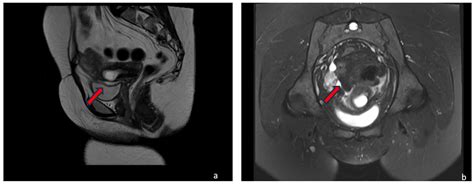

• Suspected Fetal Anomalies: MRI can provide detailed images of the fetus, helping to detect and diagnose congenital anomalies that may not be visible on ultrasound.

• Placental Abnormalities: MRI can help identify placental abnormalities, such as placenta previa or placental abruption, which can pose risks to both the mother and the fetus.

• Maternal Conditions: MRI can be used to diagnose and monitor maternal conditions that may affect pregnancy, such as pelvic pain, back pain, or neurological symptoms.